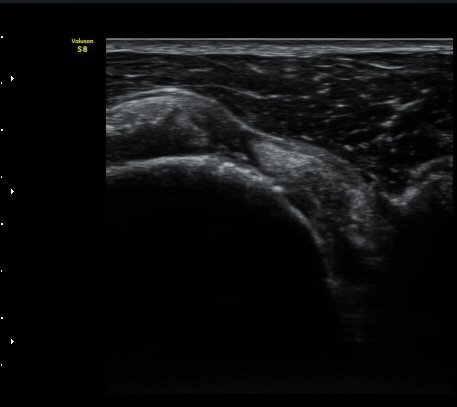

À̵Π¹Ú±Ù°Ç Ⱦ´Ü¸é°Ë»ç¿¡¼­ ƯÀÌ ¼Ò°ßÀ» º¸ÀÌÁö ¾ÊÀ½(»çÁø 1)